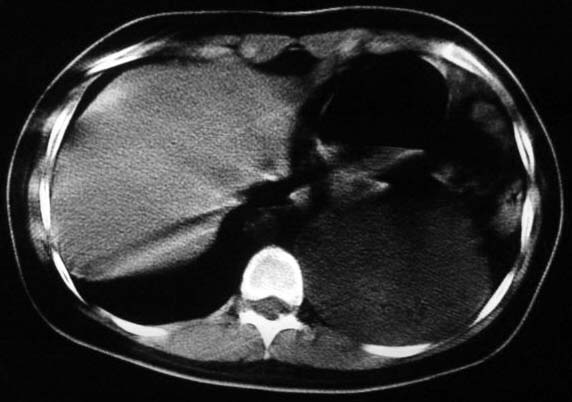

标题: CT5517:女性、24岁,反复胸痛、气促不能平卧半月。 [打印本页]

标题: CT5517:女性、24岁,反复胸痛、气促不能平卧半月。

左侧气液腔与胃腔影相连,考虑膈疝。钡餐检查有助于诊断。

左侧气液腔与胃腔影相连,考虑膈疝。钡餐检查有助于诊断

支持膈疝,纵隔窗内可见消化道的内容物。

左侧气液腔与胃腔影相连,考虑膈疝。口服urografin检查有助于诊断。

液气胸 怎么会有2 个大腔?

还是个膈疝